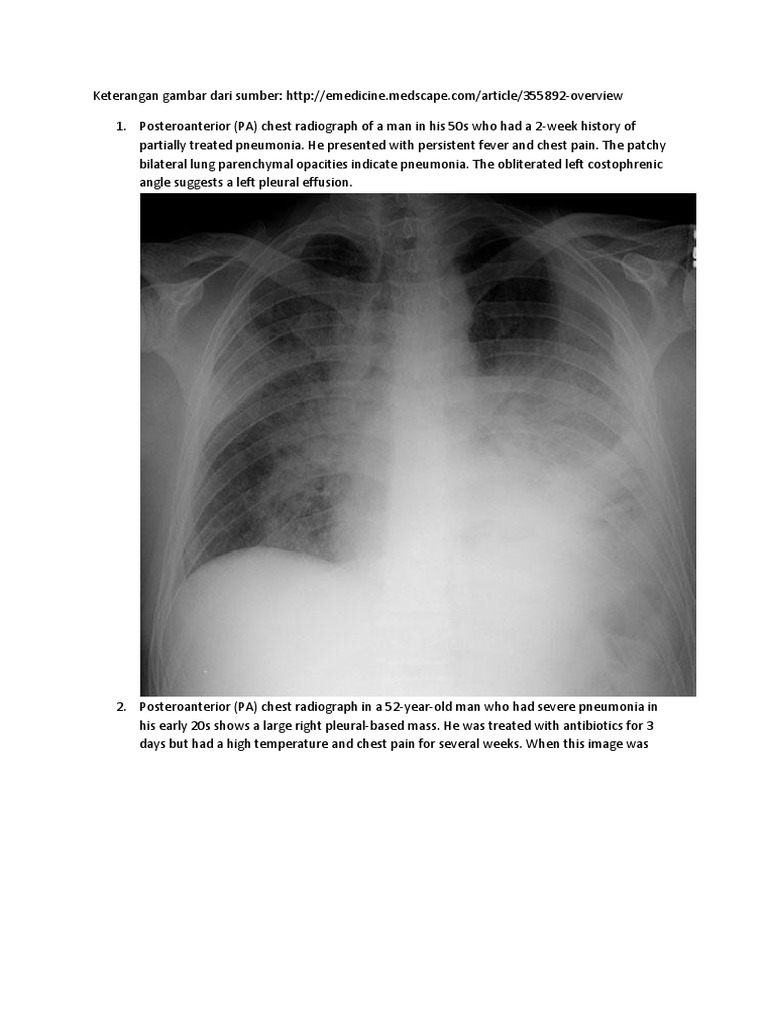

Pf2x7cuyd Ri5m